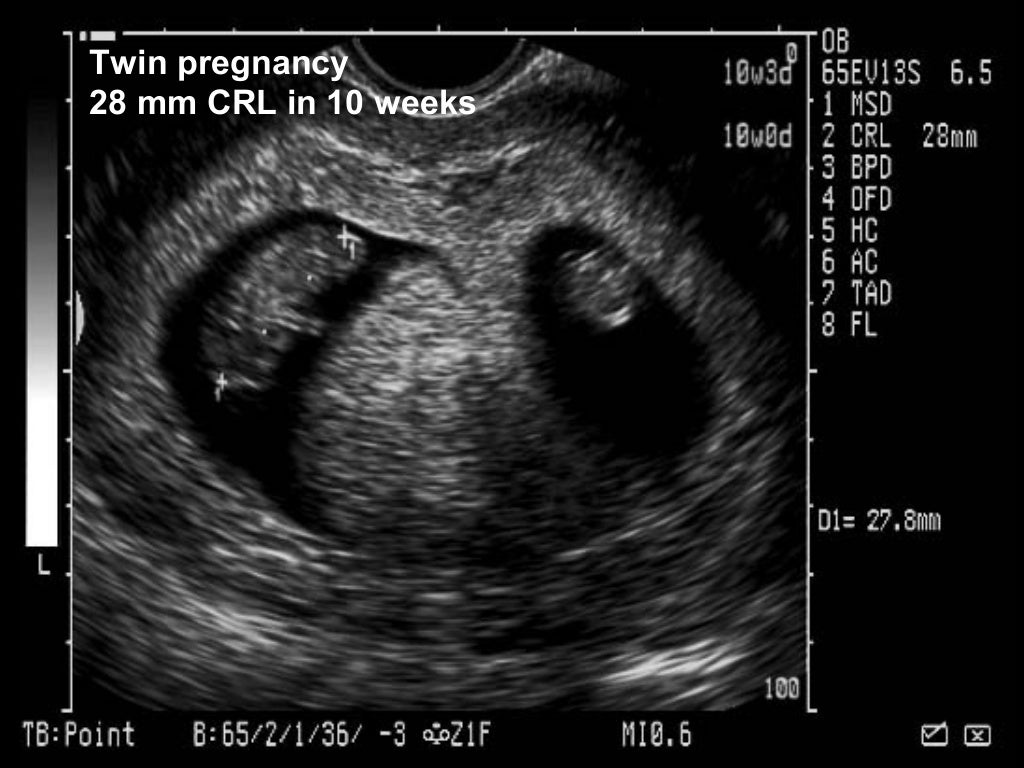

Obstetric ultrasound Baby Growing In Tubes An ectopic pregnancy occurs when a fertilized egg attaches to a fallopian tube (or, in rare cases, elsewhere in the body) as it travels to the uterus. How common are ectopic pregnancies? An ectopic pregnancy is when a fertilised egg implants itself outside of the womb, usually in one of the fallopian tubes. An ectopic pregnancy happens when a fertilised. Baby Growing In Tubes.